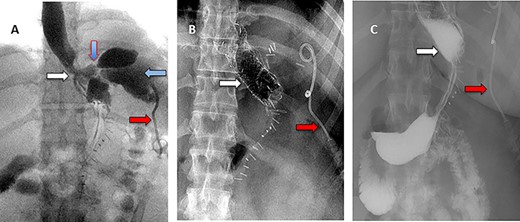

A 36-year-old obese female patient underwent a sleeve gastrectomy abroad. Eleven days after surgery, she presented with an abdominal pain. Abdominal computer tomography (CT) revealed several fluid-air collections (3 abscesses) around the upper greater gastric curve (3.5 × 3.2 cm), lesser sac (7 × 3.3 cm) as well as anterior to the spleen (7 × 3.3 cm). By that time, there was also left pleural effusion and atelectasis of the left lower lung lobe. On the next day, CT-guided aspiration was done (Fig. 1) and a pigtail catheter was inserted to drain the abscesses. On the following day, water-soluble oral contrast displayed an active contrast leak along the proximal sleeve gastrectomy (Fig. 2). On the same day, covered esophageal stent was placed endoscopically. The patient was discharged home and was scheduled for stent removal after 2 weeks. However, after 2 days, the patient presented again with an abdominal pain. The plain x-ray showed slippage of the stent distally. Upper GI endoscopy was done, and the esophageal stent was removed. One day later, the patient condition deteriorated with a massive upper GI bleeding. A CT angiography showed no extravasation and the source of bleeding was not identified during endoscopy due to massive bleeding. An immediately performed angiogram revealed an AEF (Fig. 3). The interventional radiologist achieved transient cessation of the bleeding through embolization of the fistula with interlock coils (Fig. 3). An aortogram showed continuous extravasation of contrast through the fistula, and therefore, endovascular intervention was performed with implantation of 22 mm × 112 mm aortic stent (TEVAR using Valiant covered stent - Medtronic company, USA). One week after TEVAR, another long esophageal stent was positioned (from lower esophagus to the stomach). Two weeks later, a barium swallow proved no evidence of contrast leak. Then, the esophageal stent was removed, and the patient was discharged home. There was a plan for definitive reconstruction procedure, including removal of the endovascular stent and use of reconstructed pericardial bovine graft, however, the patient declined. About 10 months later, she presented with another attack of massive hematemesis, with a drop of hemoglobin to 8 g/dl and a blood pressure of 66/44 mmHg requiring a rapid sequence induction and infusion of packed red blood cells. An immediate abdominal CT showed evidence of peri-stent infection with no contrast extravasation. Upper GI endoscopy showed an evidence of an ischemic ulcer above the Z-line with granulation tissue at the ulcer edge and erosion of the endovascular stent into the lower esophagus. The patient had a positron emission tomography (PET) scan and diagnosed with mediastinitis due to aortic stent infection and septic shock (Fig. 4). Surgical intervention was offered but the patient declined. Treatment with broad spectrum antibiotics and blood transfusion were administrated as required. Around 5 weeks later, the patient developed massive upper GI bleeding requiring intubation and surgical intervention (distal esophagectomy with removal of the endovascular stent and resection and replacement of the AEF site with reconstructed tube using 14 × 9 cm bovine pericardial graft through left thoraco-abdominal incision utilizing left cardiopulmonary bypass and distal perfusion through left femoral artery (Fig. 5). Closure of the stomach with gastrostomy tube insertion for feeding had been performed. One and half year later, reconstruction surgery of the esophagus with colonic interposition was done. After 3-year follow-up, the patient was doing well with no complication.

Esophagogastroduodenoscopy revealed thoracic endovascular aortic stent can be seen in the distal esophagus. (B) PET scan showing increase FDG activity around the distal aortic stent.